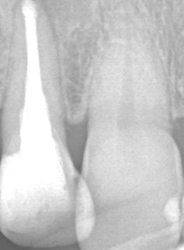

こちらのレントゲン写真を見てください。どちらかの歯医者さんで神経を取っています。根管に入れる薬は白く映ります。赤矢印部分です。一番右側が模式図ですが、青い部分が薬、根っこの先の赤点が化膿している部分です。

薬がほとんど入っていないのがわかります。黄矢印部分です。青矢印まで薬が入らないといけないのですが、全く入っていません。その結果、根っこの先が黒くなっています。膿が貯まって化膿すると黒く写ってくるのです。

別な歯科医院で治してもらいました。薬が根の先まで入っているのがわかります(黄矢印)。 根尖の黒い影が消失しています(赤矢印)。骨が再生すると白く写るようになります。

①の写真はどちらかの歯医者さんで神経を取ってもらったレントゲン写真です。根っこの中に薬が全く入っていません。

②の模式図で青く描かれている部分が薬です。

根の先を見ると小豆ぐらいの大きさの黒い影が見えます。根の中でばい菌が繫殖し感染を起こすとこのような黒い影ができます。黒い影の部分は膿(ウミ)が貯まっています。こうなると腫れて痛みが出てくるのです。

③、④の写真はそれを治した後のレントゲン写真とその模式図です。白く映っている薬が根の先まできちんと入っているのが確認できます。そして根の先にあった黒い影が消えているのが分かります。根の先の炎症が治って、骨が再生すると白く映るのです。

実はこのケース、歯医者さんの神経を取る治療でこのような根っこの病気になってしまったのです。そこでこの患者さんは神経を取った歯医者さんではなく、別の歯医者さんに受診して、根っこの治療をして治したのです。